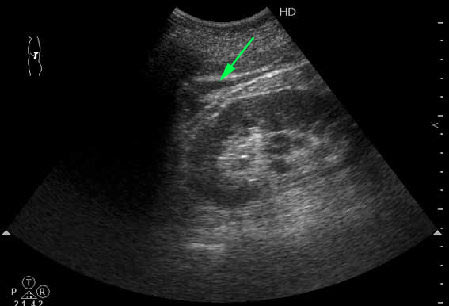

Мужчина средних лет с болями в животе.

Сонограмма выполнена из левого поясничного доступа.

Наводящий вопрос: что это (стрелка)?

- 1marked.jpg (19.21 КБ) 25438 просмотров

Что угодно ! жидкость ...